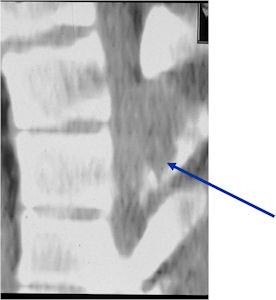

- Spine (40% of cases; usually posterior elements)

Plain X-rays:

- Geographic, circumscribed lesion usually around 5cm in size.

- There may be expansion of bone, cortical thinning and cortical breakthrough. A soft tissue mass may accompany this lesion but the soft tissue component is usually contained by the periosteum.

- The lesion may be entirely radiolucent but usually shows some degree of mineralization. Mineralization may appear stippled like cartilage but do not see chondroid pathologically. Mineralization is sometimes better detected on a CT scan rather than an x-ray.

- Usually less surrounding sclerosis than an osteoid osteoma.

- Arise from the Diaphysis (75%) more commonly than Metaphyseal (25%)

- 4 cm to 6 cm in size

CT Scan:

- More useful for detecting mineralization and evaluating extent of bone destruction than plain X-ray